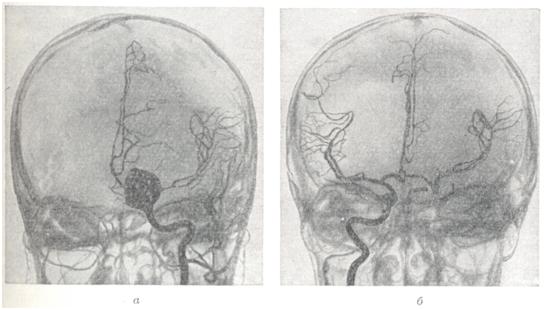

Диагноз.Появление перечисленных выше симптомов в молодом возрасте (чаще на 2—3-м десятилетии жизни) дает основание для предположения артерио-венозной аневризмы. Диагноз может быть поставлен лишь на основании всестороннего ангиографического исследования. Для выявления приводящих артерий и рано заполняющихся дренирующих вен необходима серийная ангиография с наибольшим числом снимков в первые 2—3 секунд. Лечение.Консервативное лечение является по существу симптоматическим и заключается в применении противосудорожных препаратов: фенобарбитал, дилантин и другие. При кровоизлияниях необходимо проведение коагулянтной и гипотензивной терапии. Лучевая терапия при артерио-венозных аневризмах неэффективна. Радикальным методом лечения является полное иссечение артерио-венозной аневризмы (рис. 4). Однако при большой распространенности аневризм и их расположении в глубинных, жизненно важных структурах мозга такая операция может оказаться невыполнимой. В подобных случаях могут применяться операции, уменьшающие приток крови к аневризме или приводящие к частичному выключению аневризмы,— окклюзия приводящих артерий, эмболизация артерио-венозной аневризмы и некоторые другие. Показания к той или иной операции должны быть строго индивидуальными; они определяются особенностями клинического течения, в частности количеством и тяжестью перенесенных кровоизлияний, локализацией, распространенностью аневризмы, характером ее кровоснабжения и опытом хирурга. В связи с совершенствованием техники операций, в частности широким использованием микроваскулярпой техники, показания к радикальному удалению артерио-венозных аневризм ставятся более широко, в том числе и при аневризмах, располагающихся в функционально важных зонах (речевой, двигательной). При радикальном удалении крупных, богато васкуляризируемых аневризм операцию следует начинать с выключения приводящих артерий. Благодаря этому уменьшается кровенаполнение аневризмы, а следовательно, меньше кровопотеря. При небольших поверхностно расположенных артерио-венозных аневризмах допустимо первоначальное выключение дренирующей вены; аневризма при этом наполняется кровью и более четко контурируется. Удаление аневризм, особенно расположенных в функционально важных областях, следует производить, выделяя сосудистый клубок по границе с мозгом, оставляя на поверхности аневризмы лишь тонкий слой измененного мозгового вещества. Важно при этом все время манипулировать вне пределов сосудистого клубка аневризмы, поскольку повреждение целостности ее сосудов приводит к сильному кровотечению, которое трудно остановить. Наличие внутримозговых гематом облегчает обнаружение аневризмы. Иногда гематомы как бы отслаивают часть аневризмы от мозга и тем самым упрощают ее удаление. При небольших глубоко расположенных аневризмах для облегчения их обнаружения во время операции могут быть использованы принципы стереотаксической нейрохирургии. Предварительно на основании расчетов по ангиограммам в область расположения аневризмы вводится направитель, по которому затем осуществляется подход к ней. При невозможности радикального удаления аневризмы может быть применено выключение приводящих артерий. Хотя этим путем обычно не удается достигнуть излечения и спустя некоторое время развиваются новые источники кровоснабжения артерио-венозной аневризмы, такая операция может привести к ослаблению кровотока в ней и уменьшить возможность повторных кровоизлияний. При больших, богато васкуляризированных аневризмах может быть осуществлена эмболизация сосудов аневризмы с помощью рентгеноконтрастных эмболов. С этой целью обычно используются различного размера пластиковые шарики, которые вводят через обнаженную на шее сонную (иногда вертебральную) артерию. В связи с резким ускорением тока крови в аневризме эмболы устремляются в ее сосуды. Таким образом иногда удается выключить из кровообращения значительную часть артерио-венозной аневризмы (рис. 5). Выполнение подобной операции требует точных представлений о характере кровоснабжения аневризмы, о диаметре, месте отхождения приводящих артерий и прочего. Каждый этап операции нужно контролировать повторным ангиографическим исследованием. Несоблюдение этих предосторожностей может привести к попаданию эмболов в нормальные сосуды мозга. Для направленного выключения сосудов, кровоснабжающих аневризму, а также для лечения других сосудистых поражений мозга (каротидпокавернозные соустья, некрые формы артериальных аневризм) применяют так называемые ангиотаксические операции. Смысл этих операций заключается в том, что подход к пораженному участку осуществляется по кровеносному руслу внутри просвета сосуда. С этой целью используют специальные катетеры, снабженные окклюзирующим баллончиком (Ф. А. Сербиненко, 1971). Такой катетер может быть направленно введен в приводящий сосуд артерио-венозной аневризмы посредством пункции сонной артерии на шее. Конструкция катетера позволяет произвести окклюзию сосуда, оставив в артерии баллончик, заполненный быстротвердеющим пластическим веществом, а катетер извлечь (рис. 6). Делаются попытки хирургического лечения артерио-венозных аневризм путем их замораживания с помощью жидкого азота. При аневризмах большой вены мозга, вызывающих окклюзию путей цереброспинальной жидкости, если нет условий для их удаления, возникают показания для разгрузочной операции с отведением цереброспинальной жидкости из желудочков мозга в венозное русло (вентрикуло-аурикулостомия). При тотальном удалении артерио-венозной аневризмы полностью исчезает опасность повторных кровоизлияний, прекращаются или становятся реже эпилептические припадки. Наступает нормализация кровообращения в головном мозге: при контрольном ангиографическом исследовании отмечается нормализация просвета ранее расширенных артерий, не заполняются дренирующие вены, лучше контрастируются сосуды областей мозга, прилегавших к аневризме. Летальность при тотальном удалении артерио-венозных аневризм колеблется в широких пределах и определяется прежде всего показаниями для хирургического лечения. По литературным данным, средняя послеоперационная летальность составляет приблизительно 10%, но при правильном определении показаний и использовании современных хирургических возможностей могут быть достигнуты лучшие результаты.